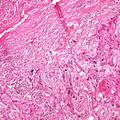

HISTOLOGY: RESPIRATORY: Lung: Carcinoma: Micro H&E low mag squamous cell carcinoma in dense fibrous stroma same case as 6